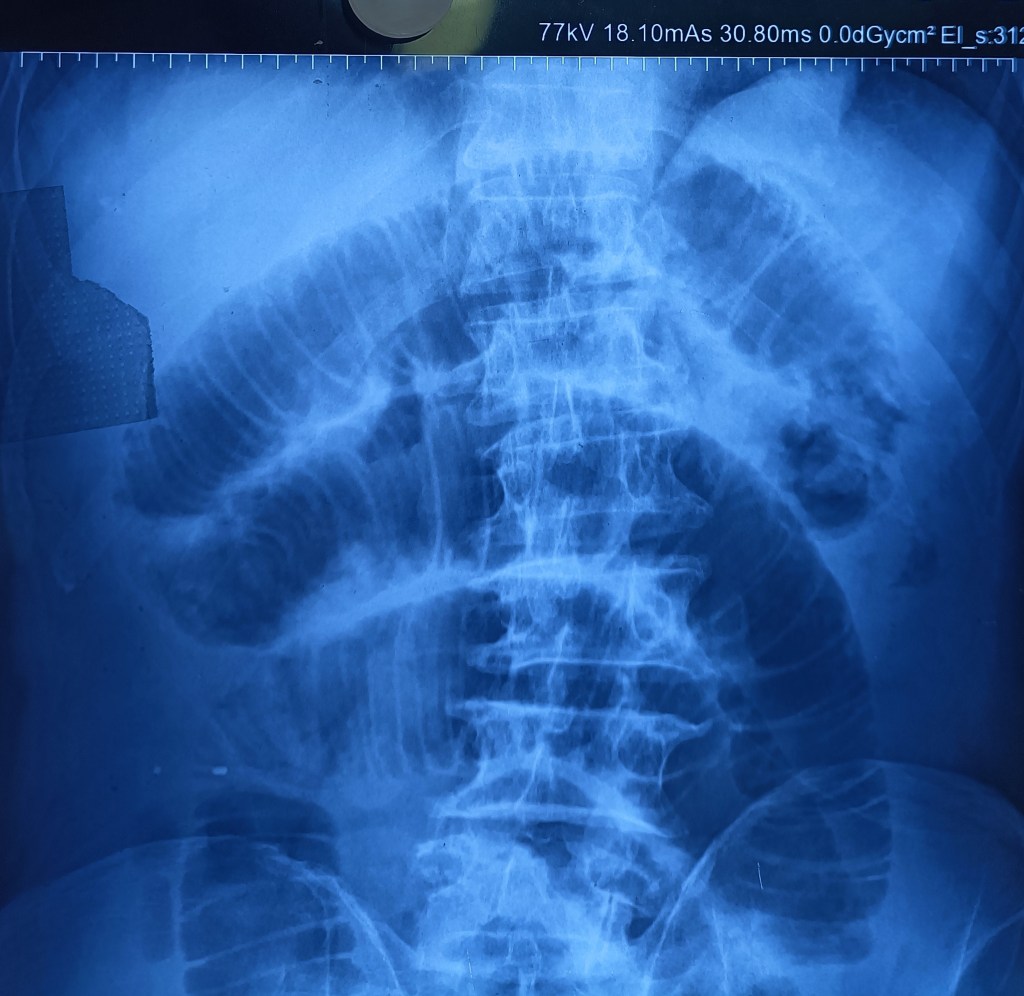

An elderly man (70 years old), a Nihang, had been having an inguinal hernia for nearly 20 years. This had now grown hugely, extending down into the scrotum, with abdominal X-ray showing signs of intestinal obstruction. However, he was adamant at not having surgery.